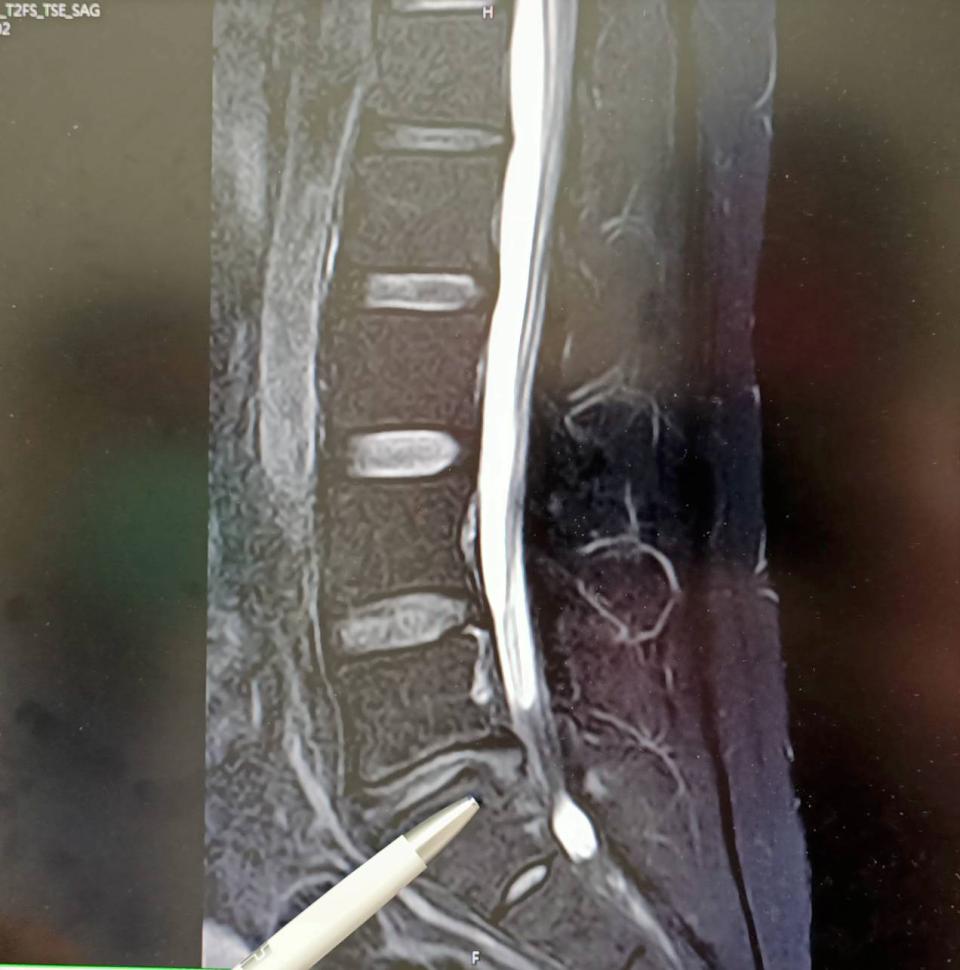

屏東市31歲男子因農務需搬重物,112年左側腰臀疼痛延伸腳踝,影響正常生活,經核磁共振檢查確認第五腰椎及第一薦椎神經壓迫,上網獲知七賢脊椎外科醫院副院長朱晟瑋病友手術成功經驗,決定來高求醫,接受無鋼釘穩定器微創手術治療,術後隔天獲得明顯改善,一週正常步行,感謝妻子悉心照料。

朱晟瑋說,臨床常見腰椎及薦椎神經壓迫肇因長期姿勢不良,無鋼釘穩定器微創術兼具安全性高、復原快等特性。 圖/七賢脊椎外科醫院提供、文/高培德